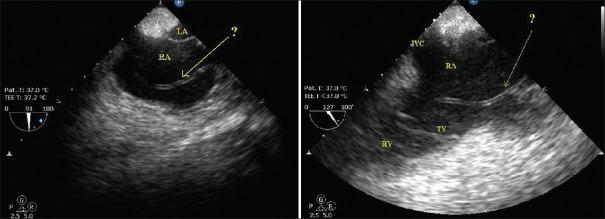

Serpentinous structure in the right atrium.

Thin, slender, filament like structure is common finding in right atrium echocardiographically. These structures generally represent embryological remnants like thebasian valve, eustachian valve and chiari network. Apart from these variants, they can also be initial finding of thrombotic process specially in the presence of central venous catheter. Early detection and removing the catheter can prevent further thromboembolism in such cases.